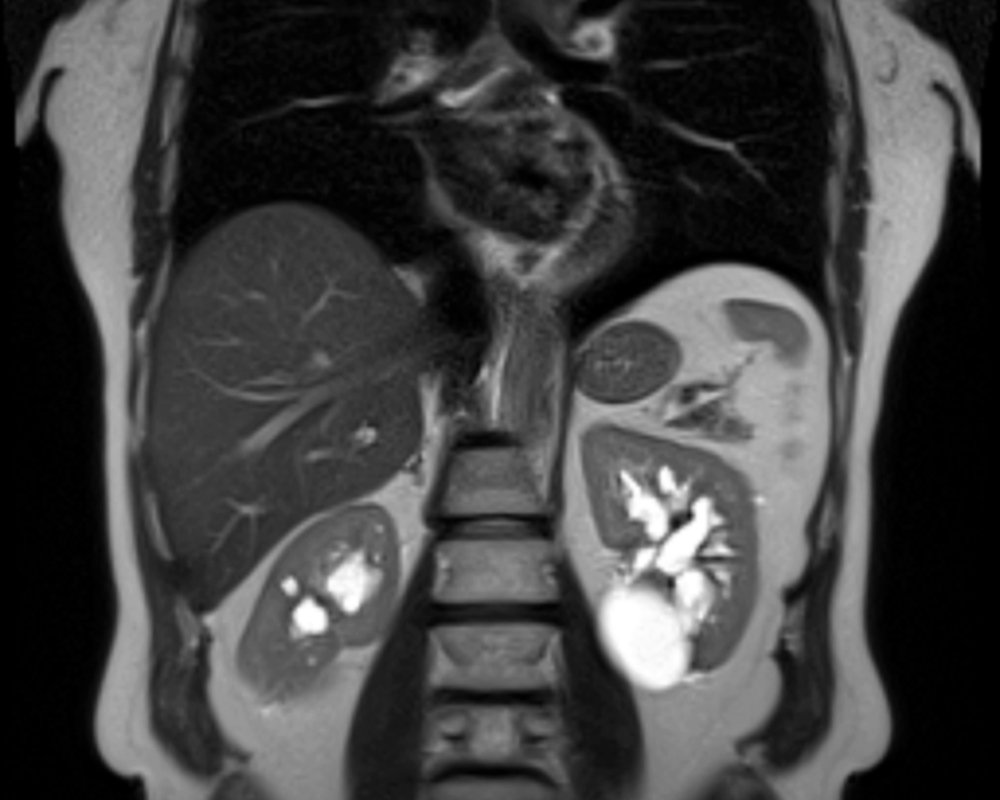

Протоколы обычно включают последовательности T2-взвешенных изображений для оценки анатомии чашек, лоханок и стенок, а также T1-взвешенных и диффузионно-взвешенных изображений для выявления патологических изменений. Параметры подбираются так, чтобы обеспечить достаточную покрывающую область и разумную временную резкость. В динамических и функциональных режимах могут применяться последовательности с контрастированием или без него, в зависимости от клиники и состояния пациента.

Оцениваются размеры, форма и положение почек, состояние чашечек и лоханок, а также структура паренхимы. Контрастирование помогает выявлять опухоли, кисты и воспалительные изменения, а также оценивать кровоснабжение и динамику оттока мочи. В некоторых случаях выполняются функциональные последовательности, которые позволяют судить о фильтрационной способности и резидуальном объёме.

При интерпретации обращают внимание на размер и форму органов, состояние чашек и лоханок, наличие камней, стенок и полостей, а также на сигнали на разных последовательностях и степень контрастирования тканей. Диффузионные изображения помогают распознавать воспаление, доброкачественные и злокачественные образования, а также структурные изменения после перенесённых операций или травм. В контексте данных оценивают вероятность обструкций и нарушения динамики мочевыделительных путей.